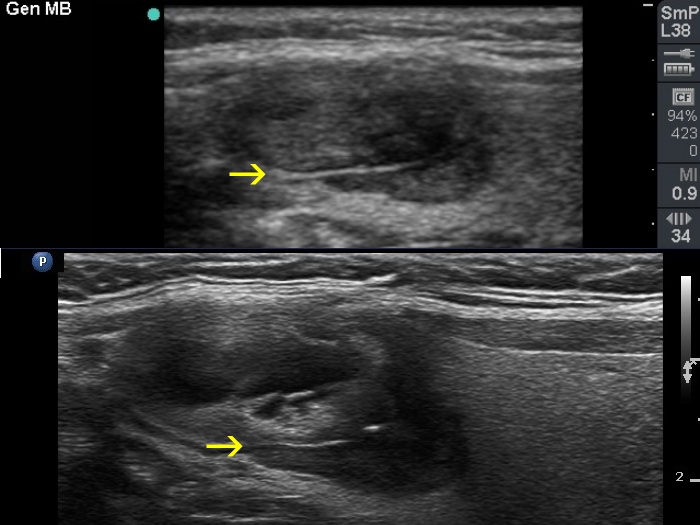

Halo sign and vascular pattern of nodules - case conp 068

Follow-up investigation seven years later (ultrasonographic picture 3c)

Right lobe, longitudinal scan. Comparison of the ultrasound patterns at first (upper image) and follow-up examination (lower image). Note that the nodule seen at the follow-up clearly as a distinct nodule had been already present at the first examination. However, at this time it did not differ in echogenicity from the larger nodule and was much smaller. Yellow arrows point to a connective tissue fiber which was present at both occasions.